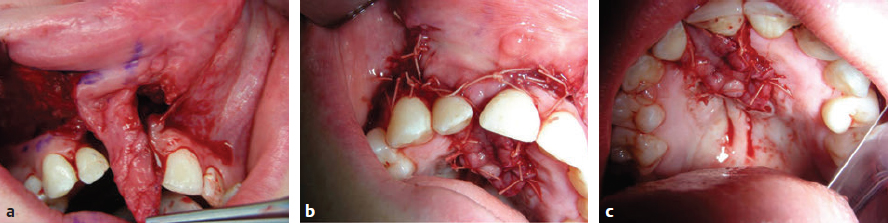

CHAPTER Patients born with cleft lip and/or palate require the care of several specialists and a number of surgical procedures and other interventions, from infancy to adulthood, to achieve total habilitation and have the opportunity to live normal and productive lives. The goals for habilitation include normalization of facial appearance and functions including improvements in soft tissues as well as skeletal, dental, and occlusal relations. Speech, hearing, and psychosocial issues are also addressed and managed. The need for multidisciplinary management using comprehensive protocols designed to address each patient’s multiple and complex needs has been well recognized, and the role of the team approach has become the gold standard of cleft care. Members are responsible for the longitudinal evaluation and coordinated care and provide for regular interactive encounters between all necessary professionals representing a variety of disciplines. They meet to communicate, collaborate, and consolidate knowledge. Extensive initial evaluation plans are made for immediate and future care based on each patient’s individual needs and the team’s treatment protocols. A prime responsibility of each team also includes careful record keeping. Collected data are studied and analyzed periodically to fully appreciate the outcome of protocols and surgical procedures, identify possible drawbacks, and modify or improve them as needed.1 Evaluation of results after cleft lip and palate repair is not easy, and several flaws are recognized in the reported outcomes of retrospective or prospective studies. Nearly 2 decades from infancy to adulthood are necessary for the completion of care and subsequent evaluation of functional and aesthetic results. Thus the final evaluation of outcomes can be problematic for several primary reasons: • Turnover of team members • Change of protocols • Introduction of new surgical procedures • Patients’ relocation • Incomplete records for services provided outside the institutions • Changes in insurance coverage • Denial of insurance coverage for some necessary services and refusal of patients to undergo final aesthetic or reconstructive procedures Many studies include a small number of patients with multifaceted problems related to the deformity, as well as significant variations in treatment protocols, timing for each procedure, surgical technique(s), and experience and skills of the individual surgeon, and many have an incomplete follow-up period.2 Furthermore, the vast majority of current studies rely primarily on subjective, not objective, evaluation. For example, evaluation of facial features using only photographs provides information about facial symmetry, but this may not be the most appropriate way to judge a surgical outcome given that only static results are displayed and asymmetries or irregularities during animation could have been missed. The need for well-planned, well-designed, ethical, multicenter, prospective long-term studies has been well recognized. Such studies could provide quantifiable, nonbiased data and assist in improving patient care by addressing remaining controversial issues, such as appropriate timing for specific surgical procedures as well as selection of the best possible surgical technique(s). Until such studies are available surgeons must rely on data from existing studies and honest evaluation and analysis of their own results to provide the best possible care for their patients. With improved knowledge and collective experience, extensive long-term follow-up studies, appropriate coordinated care, cooperation among specialists, close monitoring, and analysis of short- and long-term results, as well as adequate funding to cover all necessary services, management of patients with facial clefts could further improve so consistently superior results can be achieved. Residual deformities have several primary causes: • Failure to recognize and treat the full spectrum of problems associated with facial clefting • Tissue deficiencies inherent to the cleft • Inappropriate timing • Poorly designed and performed procedures • Complications of the initial surgery Additional operations and revisions are required to correct deformities that were not addressed during the primary procedure, inherent tissue deficiencies, maxillofacial changes, and/or scar contractures. Additional procedures might also necessary to address otologic, dental, and speech problems and to improve persisting residual functional and aesthetic deformities. These procedures have been described at length in many textbooks and scientific articles. The average number of procedures necessary to achieve the best possible functional and aesthetic habilitation has not been clearly defined, and it is difficult to accurately estimate from existing data. In some studies secondary procedures, such as alveolar bone grafts and orthognathic surgery, are barely mentioned or included, and most studies do not include dental or otologic procedures in the average total numbers. Thus the total number of procedures or interventions is definitely underreported.3 Few surgeons have reported on the actual average number of procedures required to achieve the best possible long-term results.4–7 More recently David and others8–10 presented a series of papers entitled “From Birth to Maturity: A Group of Patients Who Have Completed Their Protocol Management” that included evaluation of patients with unilateral cleft lip and palate, isolated cleft palate, and bilateral cleft lip and palate. These unique studies are based on the experience of one surgeon and a center with a relatively stable patient population. Despite the lack of detailed longitudinal data, however, there is general agreement that regardless of protocol of care, subsequent procedures will be necessary from infancy to adulthood to achieve the best possible functional and aesthetic results and complete habilitation. The objectives of primary cleft lip repair are to establish anatomy and symmetry of the upper lip and nostrils and improve form and function. Criteria for satisfactory cleft lip repair, regardless of surgical technique, are summarized in Box 40.1. The value of preoperative orthopedics and lip taping in the final outcome is still debated. Repositioning of the maxillary alveolar segments in an anatomically correct position could facilitate a tension-free closure and allow for a simultaneous periosteoplasty in selected cases. Such an approach might result in a better appearance of the lip, alveolus, and nose and potentially reduce the total number of secondary procedures. At my center we use a modified nasoalveolar molding device to improve the position of the maxillary segments and facilitate nasal repair.11 Intermediate results appear promising, but definitive final long-term results of such interventions and potential adverse effects on maxillofacial growth are only partially available.12–14 Disadvantages of this protocol include the additional expenses and the need for multiple visits for adjustment, but these could be offset by the reduction of subsequent surgical procedures. Summary Box Common Complications Related to Cleft Lip and Palate Repair Cleft Lip Cleft Palate • Dehiscence • Bleeding • Infection • Unfavorable scarring • Discrepancies of the upper lip • Intraoral (mucosal) scar contracture • Orbicularis oris deformities • Mucocutaneous deformities • Vermilion deformities • Sulcus obliteration • Combinations • Dehiscence • Palatal failures/fistulas • Scar contracture • Velopharyngeal deficiencies • Skeletal deformities • Combinations Preoperative orthopedics for bilateral clefts with repositioning of the prominent premaxilla is more widely accepted. Several techniques have been described to achieve premaxilla repositioning. We use a noninvasive appliance, fabricated by our prosthodontist, which is helpful in optimizing the position of the premaxilla and, if needed, combined with nasoalveolar molding extensions. Negative effects on facial growth and development have not been observed. Several weeks are necessary to achieve a favorable repositioning of the premaxilla and improve alignment with the maxillary segments.15 In extreme cases, and when conservative management is unsuccessful, premaxillary setback can also be used to bring the premaxilla within the occlusal plane and facilitate a tension-free lip and palate repair.16 Immediate surgical complications after cleft lip repair are extremely rare but include bleeding, infection, and dehiscence. Early wound dehiscence is rare and primarily is a result of technical errors or closure under tension or occurs after accidental trauma. In such cases, immediate management with minimal débridement, additional undermining as needed, and layered closure without undue tension is recommended (Fig. 40.1). • Detailed markings of all landmarks, taking into consideration the anatomy of the upper lip, alveolus, and nostrils • Accurate measurements and markings of all proposed incisions • Gentle tissue handling • Development of flaps on either side of the cleft with adequate tissue mobilization • Release of superficial and deep fibers of the orbicularis oris from their abnormal attachments • Dissection and reposition of the cleft-side lower alar cartilage in a more symmetrical three-dimensional position • Reconstruction of the nasal floor • Accurate skin, muscle, and mucous membrane union • Closure under minimal or no tension to achieve the optimal scar • Symmetrical vermilion border with alignment of the vermilion (dry lip) and the mucosa (moist lip) • Slight eversion of the lip, accurate reconstruction of the Cupid’s bow and the tubercle, and correct alignment of the white roll • Symmetrical nostril floors and elongation of the columella, as needed Fig. 40.1 (a) A 7-month-old patient 7 days after bilateral cleft lip repair with complete dehiscence on the left side after a fall at home. (b) After cleansing and minimal débridement. (c) The lip was repaired again in layers. (d) Two months later the lip has healed well. Residual lip deformities might vary from minor ones corrected with minimal interventions, to major asymmetries and deformities that may even require complete revision of the lip repair. It is beyond the scope of this chapter to describe all residual deformities and present all reported techniques and modifications. The most common deformities are presented with the recommended treatment and with reliable techniques based on my experience and time-honored procedures. A revision lip surgery should only be chosen after extensive consultation with the family and the child and with a clear understanding of the expectations. Objectives of the procedures, the surgical plan, and possible outcomes should be outlined and false expectations dispelled. Timing can affect the outcome and should be taken into consideration, but decisions should be individualized and not made in a rigid and dogmatic fashion. Procedures should be postponed if an adolescent is not willing to have surgery, even when parents desire and request it. Conversely, some procedures might be scheduled earlier than initially planned if there is evidence of a negative psychologic effect on the child. If possible, several procedures should be bundled to reduce time away from school or work, additional psychological trauma from multiple interventions, and cost. Before planning a revision, the entire lip, including the oral mucosa; sulcus; alveolus; and nostrils should be examined at rest and during animation. The deformity should be analyzed and all contributing factors taken into consideration. All necessary soft tissue landmarks should be appropriately marked and measured. All contributing elements to the deformity should be corrected in one setting whenever possible (Fig. 40.2). Careful planning, appropriate timing, and detailed execution are extremely important, because failure of the revision procedure to correct the deformity may result in additional scarring and tissue loss that could further reduce the chances for adequate habilitation.3,17 Wide, poorly healed persistent scars of the upper lip with unsightly stitch marks are encountered less commonly. They result from closure under tension and the use of tight sutures left in place for too long. Such problems can be avoided in most cases by using fine techniques with meticulous tissue handling and a tension-free closure, fine sutures, or even tissue adhesives. Other aggravating factors include postoperative bleeding, infection around the suture line, and dehiscence. The surgeon should be able to differentiate these unsightly scars from the hypertrophic scars that form without apparent cause and usually fade away slowly without need for additional surgical intervention. Timing for scar revision is important to the final outcome. Waiting several months before a revision to allow the scar to mature is recommended. After careful evaluation, the appropriate surgical procedure should be planned. Elliptical excision of the scar, with precise approximation and closure after limited undermining, is the simplest solution. This technique, however, can only be applied for relatively narrow scars. Excision of wider scars might result in defects that, if directly repaired, might cause distortion of the lip in the vertical or horizontal axis and/or narrowing of the nostril sill. To prevent these problems, the excision should be planed accordingly, preferably with a wavy style of excision, undermining on either side of the defect and performing tissue rearrangement as needed. Geometric tissue rearrangement with z-plasties and other techniques should be avoided, because the subsequent scar will permanently carry the marks of such designs. Dermabrasion is helpful in some cases and is primarily recommended for improvement of residual surface irregularities. Finally, single hair micrografts have been recommended for male patients to further camouflage the lip scar and allow for a moustache.18 An excessively long lip on the cleft side is truly technique related. It has been encountered with LeMesurier and the initial Tennison repairs but can result with other techniques as well. Correction is difficult, because in most instances all lip layers are involved. If the discrepancy is minor, it can be corrected with appropriate excision just below the nostril sill. If a significant discrepancy is present, however, the lip should be completely divided after appropriate markings are made and carefully repaired in layers. Fig. 40.2 The entire lip, including the oral mucosa; sulcus; alveolus; and nostrils should be evaluated and all necessary soft tissue landmarks marked and measured. A short lip results primarily from straight-line closures, inadequate rotation, and advancement techniques and scar contractures. Small discrepancies can be corrected with elliptical, diamond-shaped, or wavy excisions of the entire scar and closure after adequate undermining. If needed, a z-plasty can be designed and incorporated with the revision, preferably below the nostril sill. The drawback to such approaches is the small gain achieved and the addition of a Z-shaped scar on the lip. If a significant discrepancy exists, the only solution is to redo the lip repair, extending the rotation advancement design to increase lip height (Figs. 40.3 and 40.4). Fig. 40.3 (a,b) This 5-year-old had a significant residual deformity of the lip and nose including a short lip, dehisced orbicularis oris, and lateral flaring of the cleft-side nostril. Excess skin of approximately 1-cm width in the horizontal axis was identified during markings. (c) Excess skin with corresponding vermilion was excised, the orbicularis oris was approximated after undermining, and the nostril floor was repositioned after reduction of the skin of the sill. (d) Immediate postoperative result. Fig. 40.4 (a–c) This patient had a significant residual deformity after bilateral cleft lip repair. He had a short lip, no orbicularis contact in the midline, exposed moist mucosa in the vermilion, and bilateral scar contractures in the oral mucosa. (d) Appropriate tailoring of the philtrum, approximation of orbicularis oris muscle fibers in the midline, excision of redundant vermilion, release of intraoral scars, and coverage of the mucosal defect with sliding flaps. (e) Final result 4 months after revision with improved symmetry and balance. The tight upper lip deformity primarily occurs in patients with bilateral clefts. Local tissue rearrangement and even revision of the repair is not beneficial in most cases because of the limited tissue availability and scarring. Because of the paucity of tissue, a flap from the lower lip, an Abbé flap, should be added after all scarred tissue is removed.19 This procedure is not recommended for young children because of the temporary junction of the lips. To achieve a superior functional and aesthetic result and a balanced profile, accurate design of the dimensions of the flap to match the created defect, placement of the flap in the center of the lip to simulate the philtrum, and placement of the final scars to simulate the philtrum columns are necessary. The width of the flap should be adequately planned and narrower from the normal philtrum to encounter for subsequent widening from natural tension. The layers of the flap should be sutured carefully to the corresponding layers of the lateral lip segments and the upper buccal sulcus20 (Fig. 40.5). Fig. 40.5 (a) This woman had a very short and tight upper lip after bilateral cleft lip repair and a subsequent revision. The upper sulcus was completely obliterated. (b) Design of the Abbé flap. (c) Design of the flap and proposed areas of inset on the upper lip. (d) At 3 weeks postoperatively, before division and inset of the flap. (e,f) Final result 15 years after division and inset of the flap demonstrating improved symmetry and balance of the upper lip. (b Reproduced from Bentz ML, Bauer BS, Zuker RM. Principles and Practice of Pediatric Plastic Surgery. 2nd ed. New York: Thieme Publishing; 2016.) Reconstruction of the orbicularis oris muscle is incorporated during lip repairs. Failure to release and fully reconstruct the muscular sling or partial or complete dehiscence of the muscle repair will result in unsightly bulging of the muscle on either side of the lip scar or depressions and asymmetries that are further accentuated during anima tion, giving the lip an unnatural look. For small deformities, the lip scar can be excised and the muscle fibers identified and freed from their abnormal attachments and sutured together. When a significant deformity or dehiscence exists, a total lip repair should be planned with all anatomic elements of the lip dissected and repaired correctly (Figs. 40.6 and 40.7). Fig. 40.6 (a,b) Complete dehiscence of orbicularis oris excess skin, including partially obliterated upper buccal sulcus and excess tissue in the horizontal axis. (c) Excision of excess scar, excess skin, and vermilion according to markings. (d) Layered closure. Fig. 40.7 (a) Residual lip and nose deformity after unilateral cleft lip repair. The patient had a short lip, dehiscence of the lower third of the orbicularis oris repair, lateral fullness of the vermilion depression, scarring of the nostril sill, and lateral deflection of the lower alar cartilage with nostril asymmetry. (b) The orbicularis oris fibers were identified after undermining and reapproximated. (c) The nasal deformity was simultaneously corrected through an open rhinoplasty approach. Mucocutaneous deformities result from poor alignment of the white roll during the initial lip repair. Accurate placement of the skin suture on the white roll assists in preventing this problem. This deformity is primarily corrected with an elliptical or rhomboid excision of the scar and accurate reapproximation of the mucocutaneous junction. Only a few millimeters in vertical height can be gained with this technique. As an alternative, a small z-plasty can be used to allow for interposition of the vermilion and a skin flap and ultimately results in realignment of the mucocutaneous line. Lack of bulk or poor alignment of the vermilion can cause several deformities. Lack of bulk is primarily a result of inherent tissue deficiency, dehiscence, or failure to approximate the lower portion of the orbicularis oris muscle during the initial lip repair. To correct such deformities, the scar at the vermilion border should be excised; the fibers of the orbicularis are identified after limited undermining and approximated carefully with eversion of the margins. In the past, small local filler grafts or autologous fascial grafts were recommended. Currently, autologous fat grafting is considered to be the procedure of choice and has been added to my armamentarium.21 Minimal whistling deformities of the lip resulting primarily from scar contractures in the area of the vermilion and the mucosa of the lip can be corrected with z-plasties by placing the central limb on the existing scar. A central whistling deformity with good height of the lip occurs primarily after repair of bilateral clefts of the lip. For this residual deformity, lipofilling is also considered as long as an adequate sulcus is present and there is no mucosal contracture. Vermilion fullness on the cleft side of the lip can also be encountered. As long as the rest of the lip is not involved, this deformity can be corrected with a horizontal elliptical excision. The surgeon should be very careful to avoid overresection or mismatch between the dry and moist portions of the lip. Fig. 40.8 (a,b) After two revisions, this patient had residual deficiency of the vermilion border and bulge of the orbicularis oris muscle lateral to the lip scar. (c) Intraoral scarring and contracture accentuating the deformity. (d) Preoperative marking on the skin and vermilion. (e) Release of the intraoral scar with direct approximation of the mucosal flaps (arrows) after undermining. (f,g) Final result 2 years after reconstruction; the upper lip is well healed and soft. The upper lip might also appear short because of mucosal scar contracture or even obliteration of the sulcus (Fig. 40.8). This contracture should be released independently or managed along with other deformities of the lip. In most cases of unilateral cleft lip, release can be achieved with excision of the scar, and reconstruction of the mucosal defect and mucosal rearrangement can achieve full coverage; raw surfaces will result in further scarring, contracture, and deformity. Despite advanced techniques for bilateral cases, some patients still present with partial or complete obliteration of the upper labial sulcus.22 In such cases, the lip will appear short and retracted, with incisor and even gingival show. Complete release of the soft tissues from the premaxilla and coverage of the subsequent defect are necessary. Skin or mucosal grafts were used in the past to resurface the sulcus and complete the vestibuloplasty. The surgeon should avoid denuding the premaxilla from its periosteum, completely release the lip, suture the graft in place with absorbable sutures, and stabilize it with a small stent. I currently almost exclusively use mucosal flaps advanced from the lateral lip segments with superior results and reserve the use of grafts only for the rare occasion that the defect cannot be covered with flaps because of significant preexisting scarring of the labial mucosa (Fig. 40.9). The primary objective of cleft palate repair is to establish the anatomy of the hard and soft palate as close to normal as possible, provide an adequate mechanism for velopharyngeal function and speech, and improve middle ear function. Regardless of surgical technique, the final goal should be a palate of adequate length, with reconstruction of the muscular velopharyngeal sling, and approximation without tension. Timing for cleft palate repair has been controversial because of the potential negative effects on facial growth. Since the landmark publication by Dorf and Curtin,23 most surgeons agree that early palatoplasty, before the child’s first birthday, has beneficial effects on speech without detrimental effects on facial growth. We follow this protocol with the understanding that timing of palatal repair should not be determined by age only but should be individualized, taking into consideration anatomic findings and the patient’s health. With careful palatal dissection, complete muscle dissection and approximation, flap approximation without tension, and avoidance of large residual lateral raw areas, speech results have been superior and skeletal deformities reduced. Further longitudinal studies are necessary to fully clarify conflicting issues, but based on the existing information, it seems reasonable to recommend early palate repair for most patients to improve speech outcome. The potential negative effect on maxillofacial growth should not be overlooked; it must be taken into consideration and closely monitored.24,25 Fig. 40.9 (a) Near-total obliteration of the upper buccal sulcus in a patient after bilateral cleft lip repair. (b) After excision of the scar and exposure of the maxilla a significant mucosal defect remained. (c) Immediate postoperative result after coverage of the defect with sliding mucosal flaps. (d) Final result several months after the reconstruction; the patient has a well-maintained upper sulcus. Despite advances in techniques and better understanding of their effects on speech and facial growth, several complications or failures requiring additional surgery are still encountered. The most significant ones include the following: • Palatal repair failures and fistulas • Velopharyngeal deficiencies • Skeletal deformities (see Chapter 43) There is a wide range of reported incidence of palatal fistulas after palatoplasty, and various classifications are used. For the purposes of this discussion only fistulas presenting in areas of previous palatal repair are included. Incidence seems to be independent of the surgical technique but is significantly higher in bilateral cases. Palatal fistulas represent failures of the surgical technique and might be due to several factors from poor designs to technical errors. Such errors might include incomplete dissection or mobilization of the flaps, failure to completely detach the muscles of the soft palate from their abnormal attachment to the hard palate, incomplete approximation and suturing of all soft tissue layers, closure under undue tension, postoperative bleeding between the oral and nasal layers, or infections. Anterior fistulas just behind the premaxilla may occur in patients with wide bilateral clefts in whom, because of a paucity of soft tissues in the area, complete closure was not possible or closure under tension resulted in dehiscence.10 Fistulas may become evident immediately after the palatoplasty or may develop several years later during orthodontic treatment and transpalatal expansion. Early dehiscence, particularly in the posterior third of the soft palate, is caused primarily by errors in technique or accidental trauma. If dehiscence is identified early, it should be repaired immediately to allow for early habilitation, prevention of contracture, and subsequent shortening of the soft palate. Larger fistulas may become symptomatic, resulting in nasal regurgitation of saliva, fluids, and food particles and affecting speech, causing hypernasality and articulation disturbances. Some surgeons propose conservative management for asymp tomatic fistulas, whereas others recommend closure of even small fistulas given that regurgitation of food and liquids into the nasal cavity might result in constant irritation of the nasal mucosa. This may cause swelling, occasional bleeding, and have potential effects on breathing, speech, or oronasal hygiene. I recommend waiting for several months after the palatoplasty before closing a palatal fistula, because in the early postoperative period the tissues around the fistula are inflamed, edematous, and friable. Thus attempts for repair are more likely to fail. Reported success rates vary widely.26 Better understanding of the timing and mechanics of fistula repair increases the rate of success and significantly reduces the possibility of recurrence. Large fistulas should be closed as soon as possible, but the temporary option of an obturator should also be kept in mind (Fig. 40.10). Premaxillary setback can be used when the premaxilla cannot be retropositioned to the occlusal plane (Video 40.1). This should be done after appropriate palatal expansion and even combined with anterior fistula closure and alveolar bone grafts (Fig. 40.11). Fig. 40.10 (a) This 5-year-old had a large anterior palatal fistula with food and air escape to the nasal cavity after palatoplasty and three failed revisions. (b) An obturator was fabricated by a prosthodontist to provide temporary functional and aesthetic resolution of the problem and immediate improvement in speech. (c,d) The obturator in place. Before planning a fistula repair, the surgeon must fully appreciate the anatomy: the length of the palate, size and location of the defect, and tissue availability. The surgeon should also evaluate the movement of the soft palate and the possible inadequate dissection and release of the muscles of the soft palate during the initial surgery.3 Complete speech evaluation and even endoscopy might be necessary to obtain all preoperative information and plan management accordingly. Each area of the palate has different requirements with respect to fistula closure. The surgeon should first decide whether the surrounding tissues are adequate for the closure or whether additional tissues, brought primarily from other areas of the oral cavity, will be necessary. For small dehiscences or fistulas in the area of the uvula or soft palate with adequate palatal length and movement and with no evidence of velopharyngeal deficiency, the dehiscence or fistula should be repaired with a relatively straightforward procedure without extensive dissection. The margins of the dehiscence or fistula should be excised and the palatal scar extended anteriorly and posteriorly of the fistula, as needed, to allow for better visualization and mobilization of the nasal lining and muscles and a tension-free, layered closure (Fig. 40.12). Fig. 40.11 (a–c) This 8-year-old had significant protrusion of the premaxilla, collapse of the lateral maxillary segments, and a bilateral oronasal and anterior palatal fistula after bilateral cleft lip and palate repair. (d) Near completion of palatal expansion. (e) After completion of orthodontic expansion setback of the premaxilla allowed for simultaneous closure of palatal and oronasal fistulas and bone grafting of the maxilla. (f) Final appearance with improved facial symmetry and harmony. Fig. 40.12 (a) Dehisced uvula and posterior third of the soft palate with a dehisced muscular sling. (b) Extension of the incision to the hard palate with undermining over and under the muscles and release of the muscles from their abnormal attachment. (c) Final result after layered closure. For larger fistulas extending to the junction between the hard and soft palate, attempting to directly repair the fistula might result in undue tension with subsequent failure. Lateral relaxing incisions with undermining and mobilization of the mucoperiosteum of the hard palate will facilitate a tension-free layered closure in most cases. The muscles of the soft palate should be released from their abnormal attachment on the posterior wall of the hard palate. Failure to do so will prevent adequate muscle approximation and provide no improvement of the palate movement during speech (Fig. 40.13). A critical issue with repair of such fistulas is the adequacy of nasal lining, because failure to repair the nasal surface of the palate might predispose to contracture or recurrence. For relatively small defects a z-plasty of nasal lining flaps is adequate, whereas for larger defects the introduction of fresh tissue, such as buccal flaps, might be necessary.3 A superiorly based pharyngeal flap can be used when the palate is relatively short and velopharyngeal insufficiency (VPI) is also present. The surgeon should first consider redoing the palatal repair and retropositioning the palate at the time of fistula repair or using a pharyngeal flap to provide additional support, in conjunction with correction of the VPI (Fig. 40.14). Fistulas of the hard palate represent a different challenge. Some surgeons have suggested the use of local turnover flaps from the periphery of the fistula for nasal lining closure and the use of local rotation or transposition flaps of palatal mucoperiosteum for oral coverage. These flaps occasionally can be successful. For larger defects, I prefer to redo the palatoplasty with complete mobilization of bilateral palatal flaps; repair of the nasal lining directly or with vomer flaps, if needed; and reapproximation of the palatal flaps without tension (Fig. 40.15). When vomer flaps are not available, a patch of acellular dermal matrix can be used to completely repair the nasal defect before suturing the palatal flaps.27 I place a couple of through-and-through sutures from the palatal flaps to the acellular dermal matrix to obliterate the dead space between the two layers and provide direct contact of the matrix with the well-vascularized palatal flaps. For large palatal defects resulting from multiple interventions and failures, the options for successful reconstruction are virtually absent. In such cases, paucity of local tissues can be addressed with the addition of tissue recruited from the oral region in the form of pedicle flaps. Free vascularized flaps have also been suggested to manage extremely large defects. The surgeon should be careful when dealing with such complex conditions, individualizing the plan and designing each reconstructive procedure with extreme care, because additional failure could result in further tissue loss and magnify the defect. The surgeon must also know when to stop and remember that some patients could be better served with an obturator, which of course is not the first choice for management of fistulas but is a viable option when managing multiple failures. Fig. 40.13 (a) Residual palatal fistula in the junction between the soft and hard palate many years after palatoplasty. (b,c) Margins of the fistula were stripped from the mucosa; all layers of the soft palate including oral mucosa, muscles, and nasal lining were identified; palatal flaps were mobilized after extensive undermining to achieve a tension-free closure; and the defect was repaired in layers. (d) Final result 14 months after repair. Fig. 40.14 (a,b) Small palatal fistula with complete dehiscence of the palatal muscles and uvula and significant hypernasality. (c,d) The margins of the fistula were excised, the scar of soft palate was incised to the junction with the hard palate, palatal muscles were detached from their abnormal attachment in the hard palate, and a superiorly based pharyngeal flap was raised (arrow) and sutured to the palate. (e) The palate was then closed in layers. Fig. 40.15 (a) A large anterior palatal fistula in an 8-year-old after cleft lip and palate repair. (b,c) The margins of the fistula were incised and flaps were turned over to achieve complete closure of the nasal lining. Bilateral flaps were elevated and approximated without tension. (d) Palatal flaps were elevated to fully visualize and delineate the nasal margins of the fistula before repair. (e) Final result several months after the reconstruction, demonstrating an intact palate without fistula recurrence. Large anterior palatal fistulas not treated previously and those caused by failures of previous attempts and presenting with stiffness or lack of elasticity of the palatal tissues might require additional well-vascularized tissue for a successful closure. Tongue flaps can be very helpful in the management of such difficult cases (Fig. 40.16). Two stages are required with this technique. Eating or speaking is not restricted during the interim period. Planning and attention to all technical details are important. The extent of the fistula should be delineated completely. Turnover flaps from the margins of the fistula should be used, if feasible, to achieve full closure of the floor of the nose. The palatal tissues around the fistula should be undermined circumferentially for a few millimeters to allow for adequate insetting and suturing of the tongue flap around the defect. I prefer anteriorly based flaps designed a little wider than the size of the defect and 5 to 6 cm long to prevent tethering of the tongue during speech or eating. The flap should be about 0.5 cm thick and consist of mucosa and muscle fibers. The donor site is closed primarily, almost to the base of the flap. The flap is then inset around the margins of the fistula using absorbable mattress sutures. After 2 to 3 weeks, the pedicle is divided and inset in the posterior area of the fistula after freshening of the palatal margins. The remaining pedicle is discarded, and additional sutures are placed to completely repair the tongue defect. There have been no problems with tongue mobility or swallowing after this procedure, although there are isolated reports of negative effects on speech and articulation.28 They occur with bulky flaps, which interfere with the position of the tongue during speech and could have been prevented with careful planning, designing, and insetting of the flap. Fig. 40.16 (a) A large anterior palatal fistula after multiple interventions in an 8-year-old. (b,c) Turnover flaps from the margins of the fistula were first used to completely repair the nasal lining. (d,e) An anteriorly based tongue flap measuring 5 by 2 cm was used. (f) Tongue flap inset around the margins of the fistula. (g,h) Final result with complete healing of the fistula and excellent tongue movement. Fig. 40.17 (a) Oronasal and large anterior palatal fistulas simultaneously covered with a large labial mucosa flap at the time of bone grafting of the residual alveolar cleft. (b,c) The bone graft and palatal fistula were simultaneously covered with the labial flap. The donor site was closed primarily. Another popular technique is the use of bucket-handle flaps from the upper labial sulcus to manage large anterior defects. These flaps are random but dependable. Attention to the design and technical details is again very important. Preexisting scars from the lip repair should be taken into consideration; obliteration of the buccal sulcus should be avoided (Fig. 40.17). A paucity of tissue in the area of the junction between the hard and soft palate, in both the oral and nasal surfaces, can be managed with buccal mucosa flaps. These flaps are designed on the buccal mucosa, approximately 2 cm wide and of appropriate length to reach the defect. The base of the flap should be placed anterior to the maxillary crest and tunneled under the palatal tissues, turned so the mucosa faces the nasal cavity and sutured to the defect of the nasal lining. Alternatively, the flap can be used to replace missing oral tissue. In such cases, the palatal tissue must be incised to allow for inset of the flap.29 The buccinator and facial artery myomucosal flaps could be viable alternatives for larger defects.30,31 These flaps are dependable and have a long pedicle based on the facial and buccinator pedicles but are bulkier and sometimes difficult to deliver to palatal defects. Despite better understanding of the physiology of speech, the effects of early palate repair on speech outcome, and the improvement of surgical techniques, an average of 20% of patients will have residual velopharyngeal disturbances after cleft palate repair. This rate does not seem to be influenced significantly by the surgical technique used for the palatoplasty.32–34 Close cooperation between the surgeon and the speech pathologist is necessary to obtain appropriate data, fully appreciate the condition, and prescribe the most appropriate individualized plan. Accurate diagnosis is cardinal for a successful outcome. Before testing, a detailed history should be obtained to gain information on previous orofacial and nasal procedures, feeding or swallowing problems, nasal regurgitation, speech problems, and frequent ear infections. When surgical management of the velopharyngeal valve is anticipated, we include questions to determine whether nasal airway obstruction exists. These responses, and the results of other diagnostic tests, determine whether the nasal airway needs to be managed to increase patency before an additional resistive load, such as a pharyngeal flap, is introduced into the airway.35 Techniques and measurements used to assess velopharyngeal function generally can be classified into three categories and are summarized in Table 40.1. If after completion of a course of speech therapy and extensive evaluation a determination of a need for additional treatment is made, the following options can be considered: • Revision palatoplasty • Furlow double Z-opposing plasty • Superiorly based pharyngeal flap • Sphincter pharyngoplasty • Retropharyngeal implants or fat grafting • Prosthetic management (for nonsurgical candidates) Revision palatoplasty is recommended when the muscles of the soft palate were not properly released and the muscular sling was not properly constructed during the initial procedure.36 A double Z-opposing plasty can also be used and can provide superior speech results, because of the palatal lengthening.37,38 For relatively small gaps, fat injections in the posterior aspect of the soft palate and the pharyngeal wall are gaining some popularity.39 For most other cases, a superiorly based pharyngeal flap or a pharyngoplasty are considered to be procedures of choice.40–42 Some surgeons still recommend augmentation of the posterior pharyngeal wall with various autogenous or alloplastic materials; prosthetic rehabilitation is reserved for surgical failures or for patients with significant medical problems who are not considered good candidates for a surgical procedure.43,44 Table 40.1 Techniques and measurements of velopharyngeal function